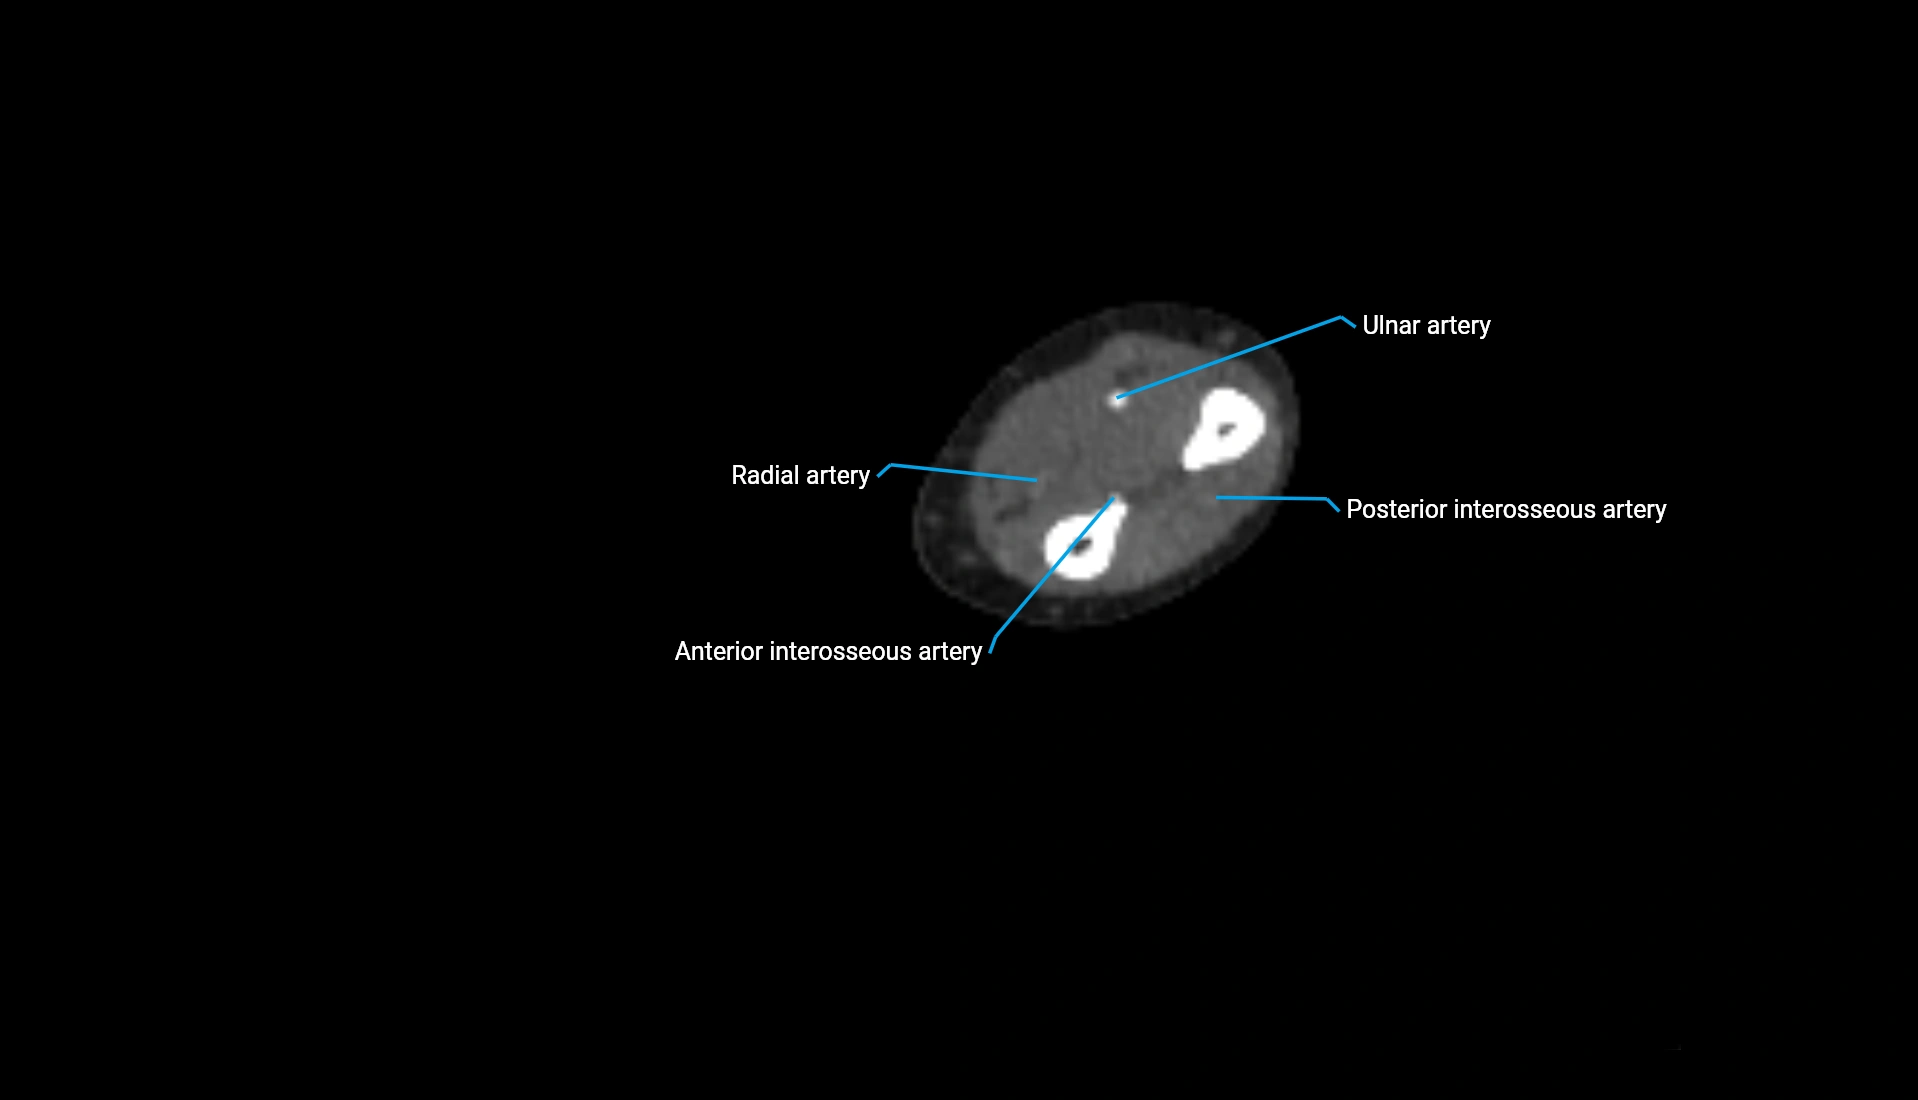

CT Appearance

Non-Contrast CT:

• Cortex: High-density, sharply defined

• Subchondral bone: Dense cancellous matrix

• Articular surface: Smooth concave contour articulating with the capitellum

• Excellent for evaluating bone integrity, alignment, and subtle fractures